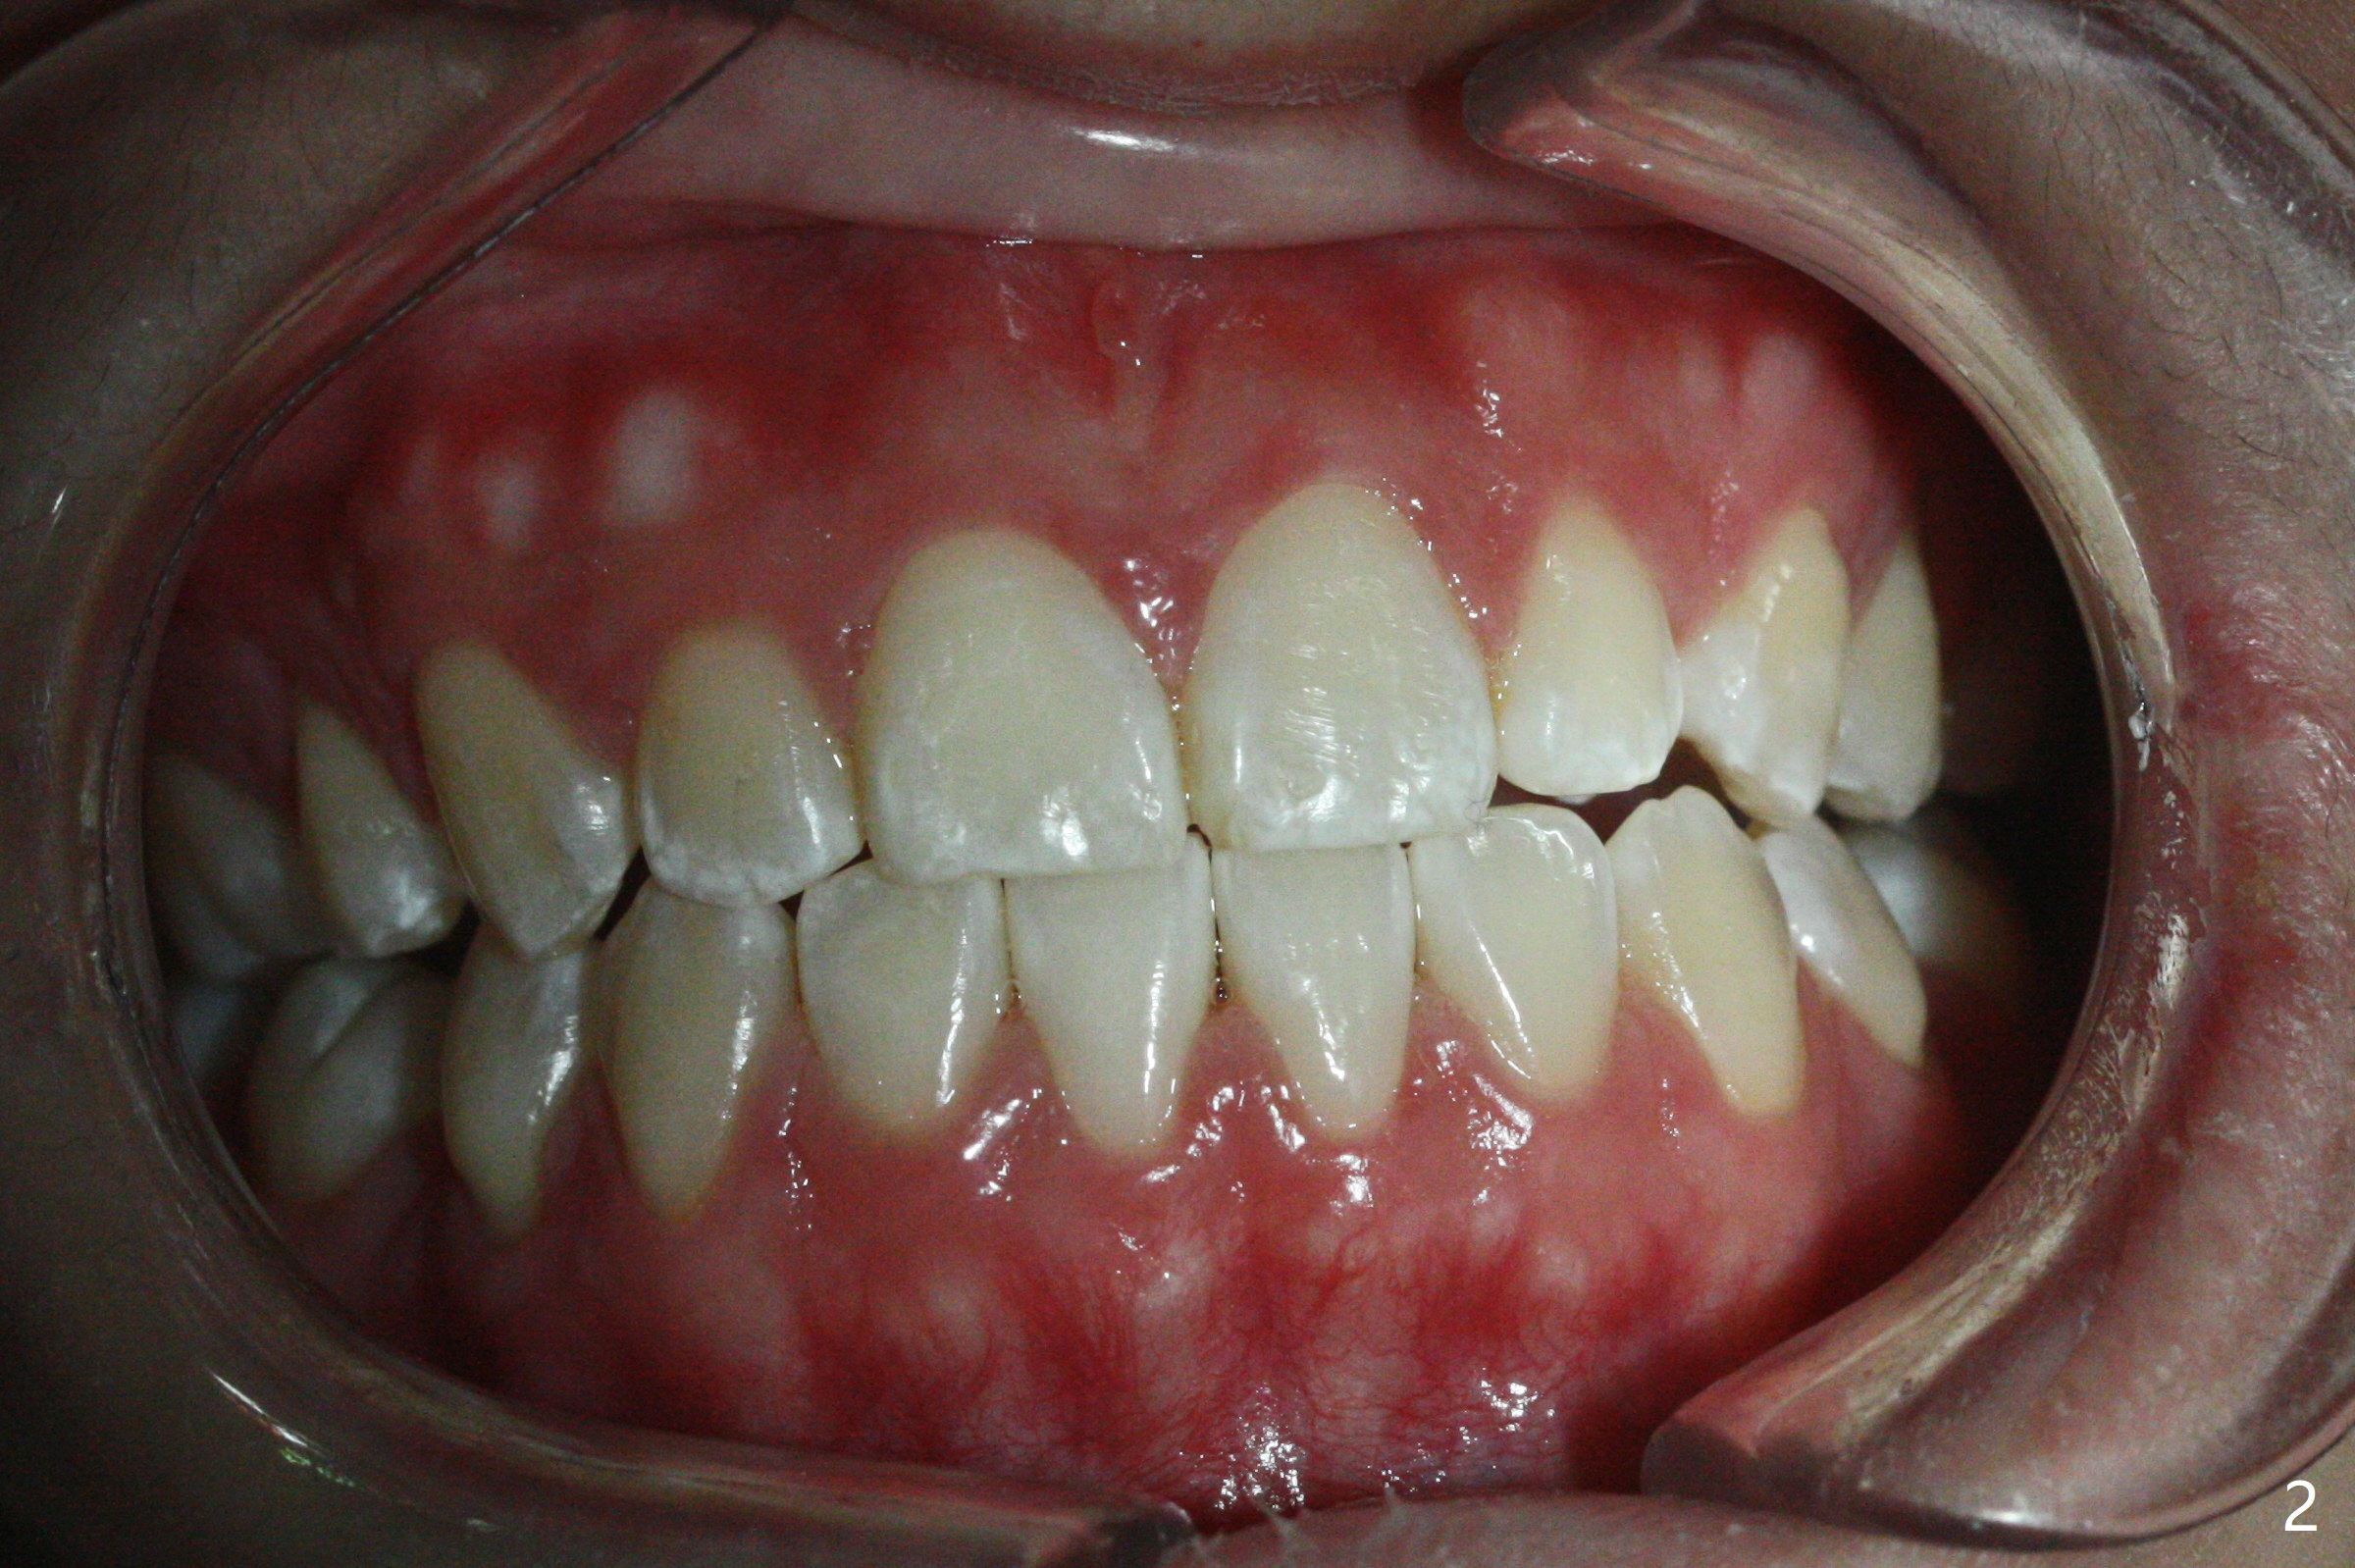

Follow Up: 2 Years 3 Months Post Debanding with UL3, LL5 Congenital Missing

A 16-year-old woman